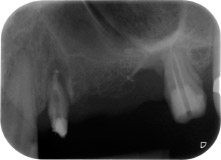

Un mois plus tard, le jour de l'intervention, la douleur et l'inflammation sur la dent 24 étaient minimes mais une mobilité de classe 2 de Miller était toujours observable. Après ouverture des lambeaux et nettoyage des tissus périapicaux et périradiculaires infectés, l'étendue du défaut osseux est devenue parfaitement visible (Figures 2 et 3).

À la racine de la dent, il manquait la totalité de l'os vestibulaire et distal. L'attache était essentiellement limitée à la racine palatine, venant ainsi confirmer le pronostic défavorable initial. La dent 27 présentait également une attache horizontale réduite et une raréfaction apicale minime (cf. Fig. 1), sans symptômes cliniques.

Nous avons toutefois maintenu notre projet initial de conservation des deux dents comme piliers temporaires d'un bridge pendant la période de six mois nécessaire à l'ostéointégration des implants. À la prochaine incision, la situation devrait être réétudiée. Premièrement, afin de gérer le problème endoparodontal, la surface de racine restante a été soigneusement débridée à l'aide d'un équipement piézoélectrique (Piezomed, W&H, utilisé avec l'insert en forme de spatule S1, initialement conçu pour limer la paroi sinusienne latérale) (Fig. 4).